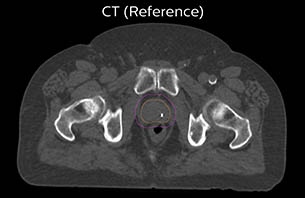

A 77-year-old male with prostate cancer cT3aN0M0, Gleason 8 and PSA 52 μg/L referred to androgen deprivation and radiation therapy with a prescribed dose of 50 Gy to the pelvic lymph node regions and 76 Gy to the prostate.

Based on the 3D T1W mDIXON images, MR-based density maps (MRCAT) are automatically generated. The VMAT (Volumetric Modulated Arc Therapy) plan is generated in TPS, based on MRCAT as primary image set. During the commissioning phase, dosimetric agreement between MRCAT-based and CT-based dose plans was studied and differences in the PTV dose were found to be minimal (<1% for most patients). Average difference in PTV mean values was 0.8% over the study group (n=62).